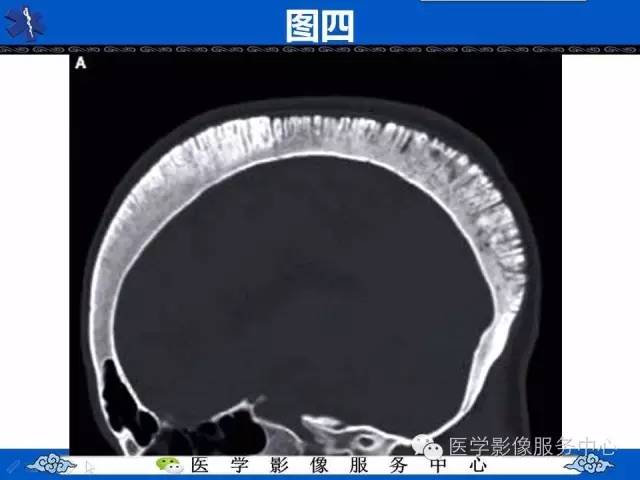

【影像征象】竖毛征——重度贫血